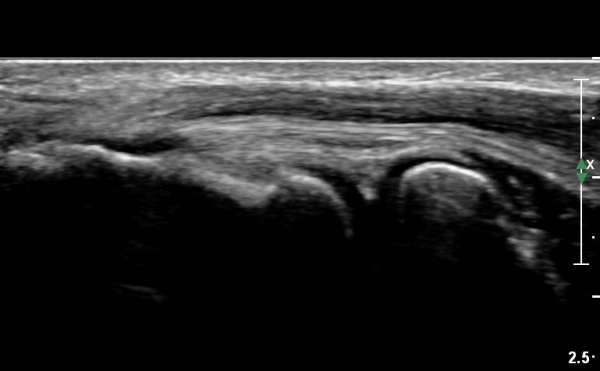

Á¶±Ý ´õ ¿ÜÃøÀ¸·Î À̵¿ÇÏ¿© °üÂûÇÏ´Ï °Ç°ú ÀδëÀÇ ÆÄ¿­ÀÌ ¶Ñ·ÈÇÏ´Ù(»çÁø 4, 5).